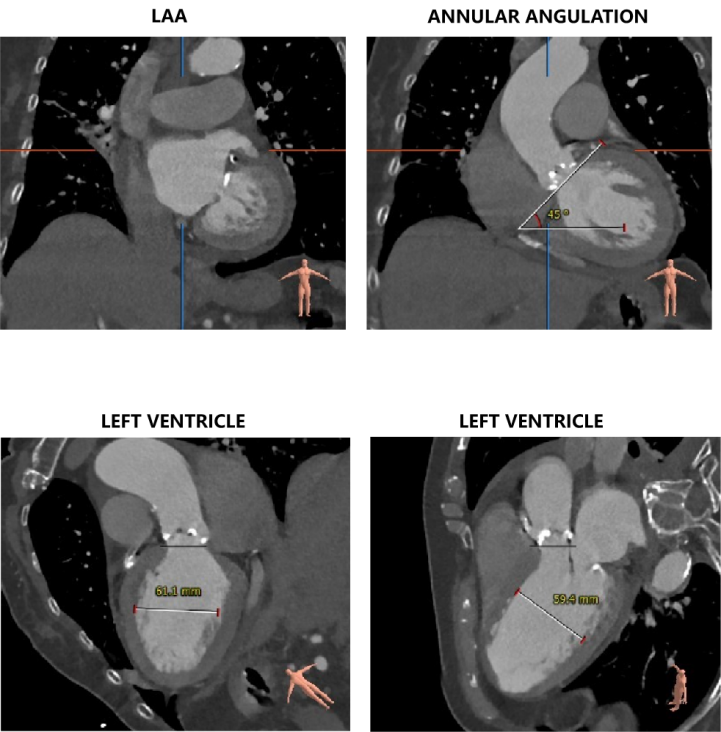

左冠开口高度11.0mm,右冠开口高度15.0mm,左冠高度较低,根据瓦氏窦内径和瓣叶长度综合判断,左冠堵塞风险不高;右冠瓣叶长度较长,存在一定封堵风险,合并患者原有冠脉疾病,考虑右冠灌注不良风险较高;左室腔增大,心室壁未见明显增厚。

②患者左冠瓣冗长,结合瓦氏窦内结构,存在较大左冠封堵危险,右冠瓣叶长度较长,合并患者原有冠脉疾病,右冠灌注不良风险较高;

④患者心功能较差,循环崩溃风险较高。